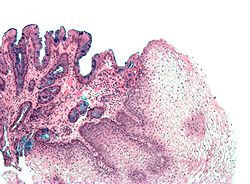

Preneoplastic

Barrett esophagus

Esophageal adenocarcinoma

- AKA adenocarcinoma of the esophagus.